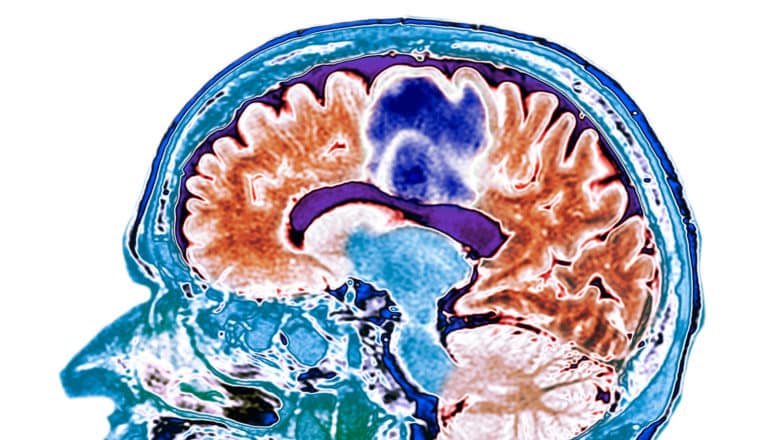

A brain scan shows glioblastoma highlighted in blue.